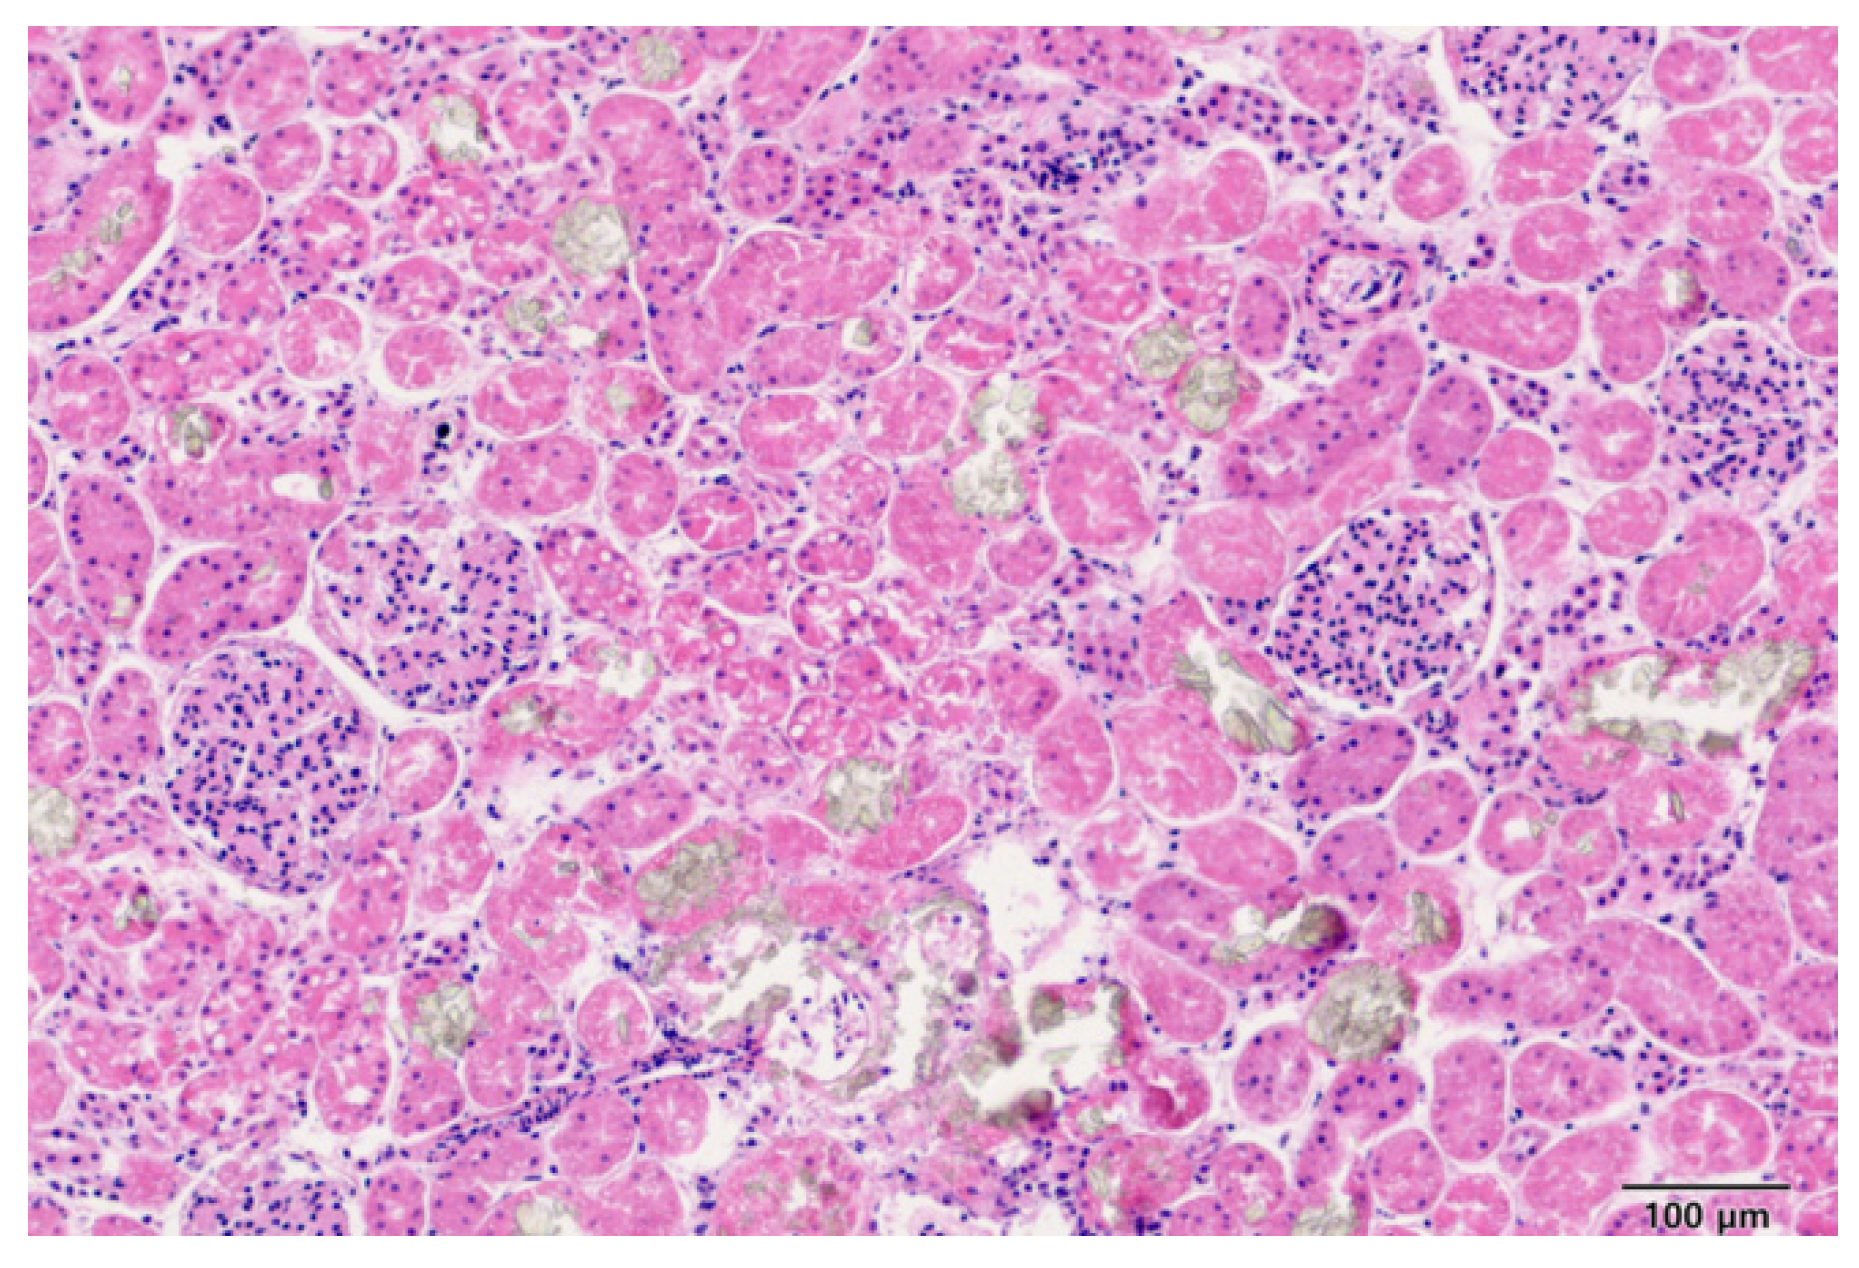

4.6. Forensic Examination [Necropsy and H&E Staining]

| 1 | Age: - Sex: Male Weight: 3.23 kg Location: Suwon | EG | 82 | 69 | 67 | Upper GI tract bleeding, mild calcium oxalate crystals within the kidneys |

| 2 | Age: - Sex: Female Weight: 4.8 kg Location: Seoul | EG | 572 | 395 | 367 | Calcium oxalate crystals within the kidneys |

| 3 | Age: - Sex: Female, Weight: 4.6 kg Location: Seoul | EG | 590 | 473 | 359 | Calcium oxalate crystals within the kidneys |

| 4 | Age: - Sex: Male Weight: 4.2 kg Location: Seoul | EG | 541 | 313 | 410 | Calcium oxalate crystals within the kidneys |

| 5 | Age: - Sex: Female Weight: 3.1 kg Location: Gimcheon | EG | 497 | 387 | 340 | Calcium oxalate crystals within the kidneys |